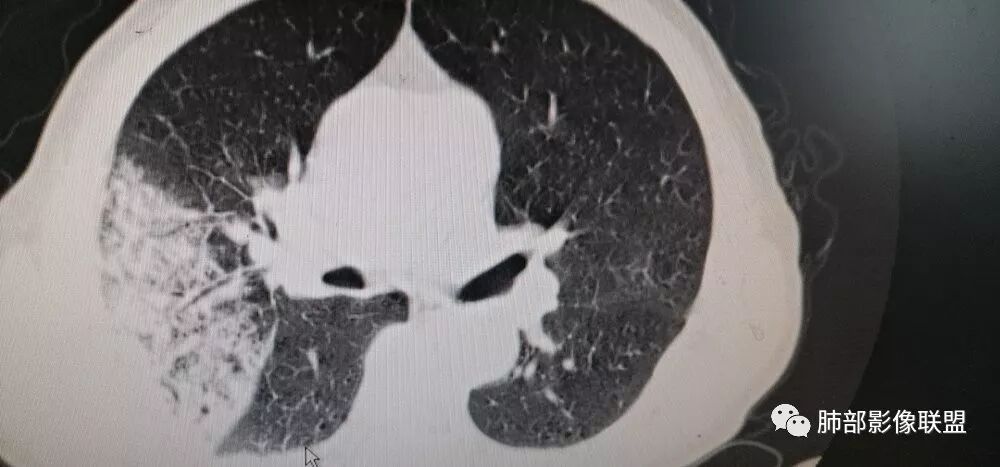

支气管充气征(空气支气管征)见于:炎症实变(大叶性肺炎,机化性肺炎,隐球菌),淋巴瘤,粘液腺癌(肺炎型肺癌),肺间质病;

管腔 :正常、扩张、狭窄或闭塞

管壁:光滑、毛糙

支气管树形态:正常(走形柔软、自然),异常(走形僵直、不完整)

分型:

I型青枝型所显示的支气管管腔未见明显改变,走行自然,整个支气管树柔软状如青树树,名为青枝型(炎症多)。

Ⅱ型,所显示的充气支气管管腔以扩张为主,名为扩张型(淋巴瘤多,原理为支气管平滑肌受累)。

Ⅲ型,显示支气管管腔狭窄与扩张并存,小分枝残缺而使支气管树形态不完整,支气管走行僵直,状如枯枝,命名为枯枝型(腺癌多)

Ⅳ型,支气管充气征与支气管黏液征并存,名为复合型。

我觉得纵膈窗可以更好观察,纵窗看支气管很紊乱的感觉,鉴别,肺炎的支气管充气征,支气管走形还是很自然的

3.病灶内支气管走形略显僵直,侧支少(粘液阻塞),也符合肺腺癌的枯树枝征。而大叶性肺炎的支气管是管壁光整、通畅、自然,结核的支气管常常壁增厚,甚至狭窄后扩张;